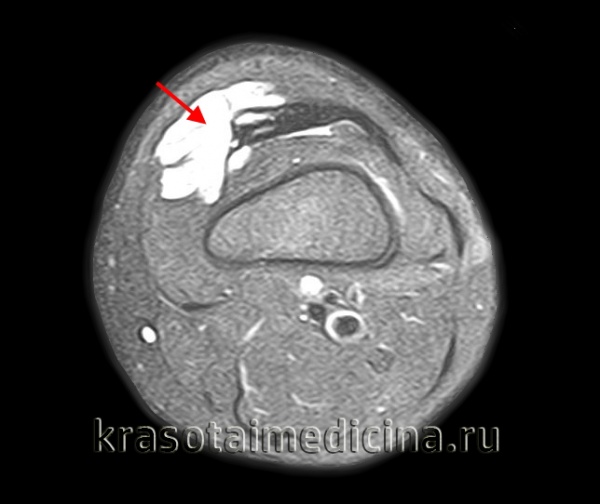

Ишемическая контрактура Фолькмана – это сгибательная контрактура кисти и пальцев, возникшая на фоне сдавления мышц при травме. Проявляется когтеобразной деформацией с ограничением активного и пассивного разгибания. Диагностируется на основании анамнеза, клинической картины, данных рентгенографии, электрофизиологических методик, УЗИ периферических нервов. На ранних стадиях проводятся консервативные и оперативные мероприятия для устранения сдавления мышц. В последующем применяются медикаментозные и физиотерапевтические восстановительные методики, выполняются хирургические вмешательства.

Больной предъявляет жалобы на нарушение функции. При осмотре обнаруживается типичная когтеобразная деформация – кисть пронирована (развернута ладонью книзу), лучезапястный сустав, межфаланговые суставы находятся в положении сгибания, пястно-фаланговые – в положении разгибания. При попытке пассивного выпрямления пальцев сгибание лучезапястного сустава резко усиливается из-за укорочения сухожилий. Выявляются расстройства чувствительности, обусловленные дегенерацией нервов.